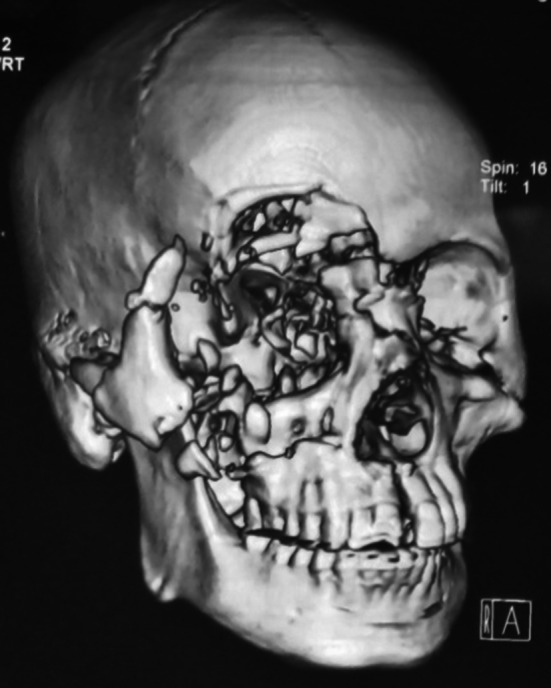

Fracture lines those were severely comminuted (Figs. 2, 3 and 4), sagittal fractures (Fig. 5), involving orbital complex, orbital floor fractures (n = 20) (Fig. 6), fractures associated with globe injuries and fracture lines characteristically involving the body of zygoma but not the processes were included in atypical group (Fig. 5).

Fig. 2.

Comminuted fractures

Fig. 3.

Comminuted fractures

Fig. 4.

Comminuted fractures